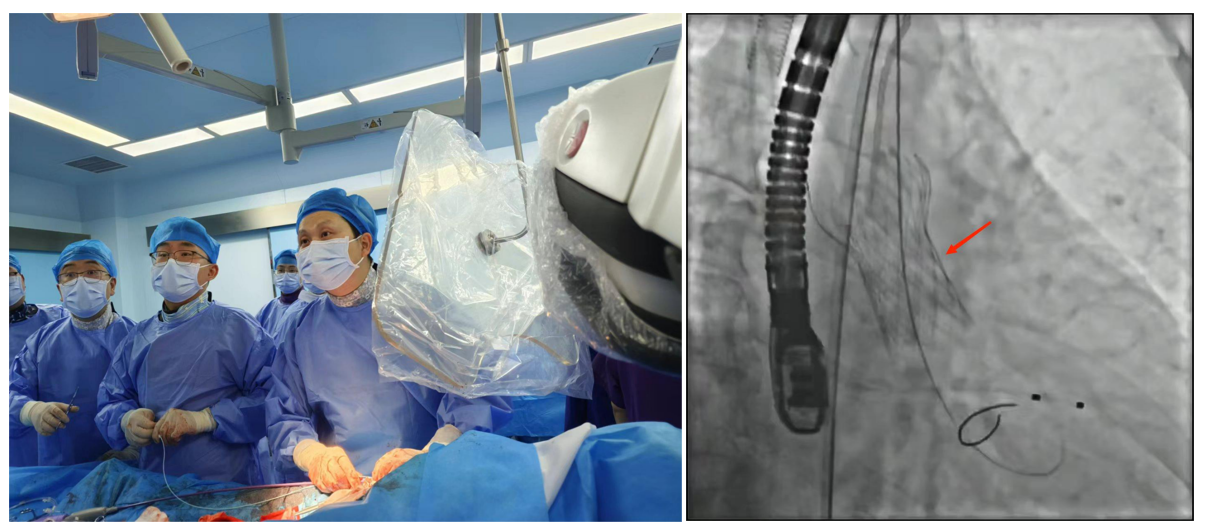

1.經皮冠狀動脈介入治療(PCI):是用心臟導管技術疏通狹窄甚至閉塞的冠狀動脈管腔,從而改善心肌血流灌注的一組治療技術。在血管嚴重狹窄或閉塞病變段放置支架或藥物球囊,以保證血管長期暢通,是冠脈介入手術的主流。

適應癥:慢性穩定型冠心病、不穩定型心絞痛、非ST段抬高型急性心肌梗死、急性ST段抬高型心肌梗死、PCI術后再狹窄或并發癥。

經皮冠狀動脈介入治療(PCI)